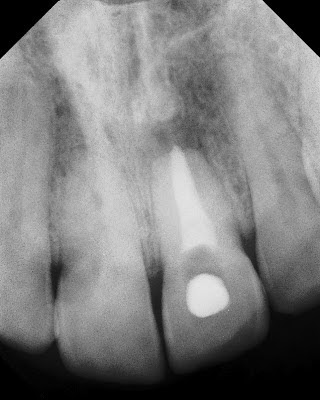

Not a surprising root canal on a 5th grader. The apex is open, root is short, and the clincian probably did the best he could to obturate this tooth on such a young patient. Please note the normal bone and gingival tissues around the tooth. So this root canal has survived 30 years without symptoms and preserved the periodontium.

Our diagnosis was: Prior RCT w/ Asymptomatic Apical Periodontitis. The tooth was currently symptom free, but had slight mobility and an obvious apical lucency.